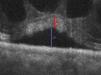

Análisis de factores pronósticos por tomografía de coherencia óptica de dominio espectral en el edema macular quístico pseudofáquico

Analysis of prognostic factors by spectral-domain optical coherence tomography in pseudophakic cystoid macular oedema